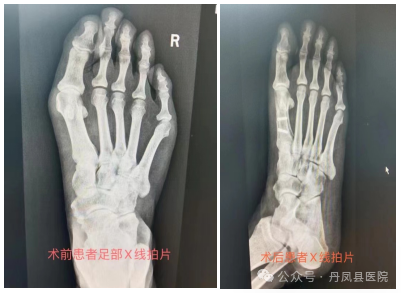

病例二:患者张某,女,42岁,左足拇外翻畸形3年余,行走疼痛,已严重影响到日常生活,经多方打听,来到我院骨一科就诊。收治入院后,骨一科主任李静宏带领科室团队为其进行了全面的足部检查,充分评估病情,研究手术治疗方案,最终成功为患者实施了拇外翻矫形术。术后患者恢复良好,并不停的称赞:“丹凤县医院医生的技术太好了,使我摆脱了多年来“大脚骨”的烦恼。”

![]()

图为患者术后足部图片